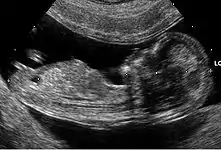

Échographie

Aucun signe échographique n'est symptomatique de la trisomie 21. Néanmoins, un certain nombre d'anomalies mineures ou majeures qui se rencontrent plus fréquemment dans cette maladie chromosomique peuvent être mis en évidence.

- Anomalies mineures

- hypoplasie ou absence des os propres du nez ;

- fémur court, inférieur au 5e centile pour l'âge ;

- épaisseur de nuque supérieure à 6 mm à 20 semaines ;

- écartement important entre les premier et deuxième orteils ;

- brièveté de la deuxième phalange du cinquième doigt (brachymésophalangie) ;

- langue protruse…

- Anomalies majeures

- des malformations cardiaques (canal atrio-ventriculaire et en particulier) (dans 40 % des cas) ;

- des sténoses digestives (dans 10 à 18 % des cas) (image en « double bulle » de sténose duodénale).